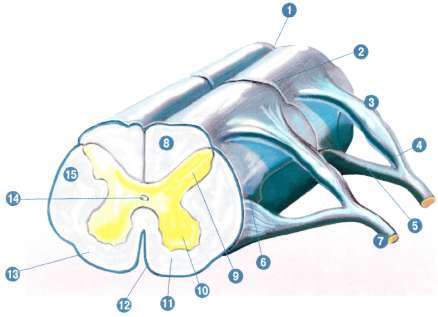

Расположение спинномозговых узлов, выход спинномозговых нервов.

Спинномозговая жидкость, центральный канал, оболочки спинного мозга, строение спинного мозга: серое и белое вещество.

Спинной мозг располагается в спинномозговой жидкости, которая выполняет роль тканевой жидкости, гарантируя постоянство внутренней среды, и спинной мозг предохраняет от сотрясений и толчков.

Вокруг центрального канала находится серое вещество, которое состоит из тел нейронов, а также их дендритов. Серое вещество на поперечном разрезе имеет вид бабочки, посмотрите на рисунок

Рис. 4. Спиной мозг в разрезе.

Белое вещество расположено в наружной части спинного мозга.